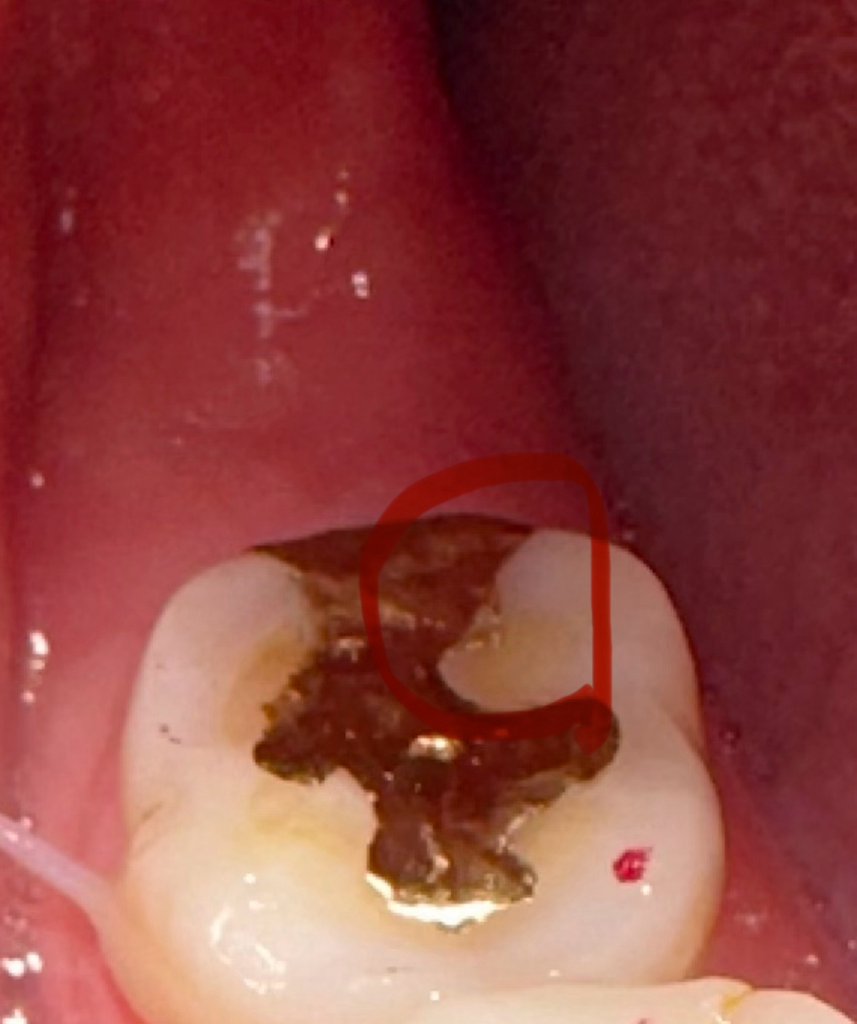

보철물을 다듬었는데 딱딱한게 씹혔는데 그게 음식인지 보철물 일부가 떨어져나간건지 모르겠어요 ㅠㅠ 위에가 오늘이고 밑에가 어제 입니다 ㅜㅜ 오늘 딱딱한게 씹혀서 찍어보니 뭔가 살짝 모양이 바뀐것같기도해서요.. 일부만 떨어져 나가는 경우도 있나요?

• 1번 째 사진

보철물이 일부만 떨어져 나가는 경우도 있습니다. 사진상으로는 떨어진 것이 확실해보이진 않습니다.

일부만 깨져서 떨어나가는 경우도 있을 수 있습니다 다만 사진상으로는 크게 차이가 나는 부분이 없습니다